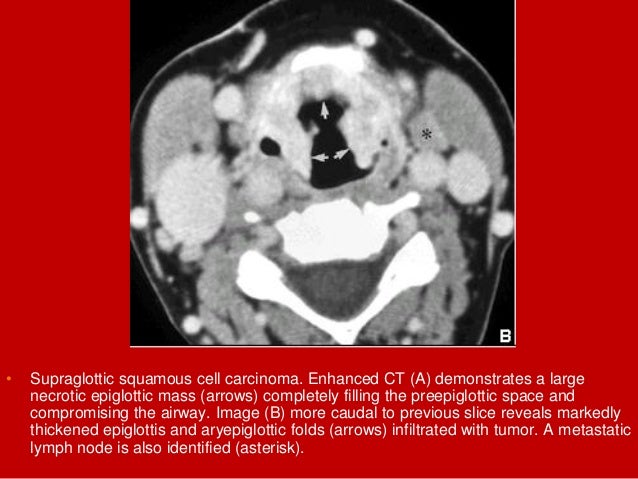

16. 16. • Supraglottic squamous cell carcinoma. Enhanced CT (A) demonstrates a large necrotic epiglottic mass (arrows) completely filling the preepiglottic space and compromising the airway. Image (B) more caudal to previous slice reveals markedly thickened epiglottis and aryepiglottic folds (arrows) infiltrated with tumor.

17. 17. • Supraglottic squamous cell carcinoma. Enhanced CT (A) demonstrates a large necrotic epiglottic mass (arrows) completely filling the preepiglottic space and compromising the airway. Image (B) more caudal to previous slice reveals markedly thickened epiglottis and aryepiglottic folds (arrows) infiltrated with tumor. A metastatic lymph node is also identified (asterisk).